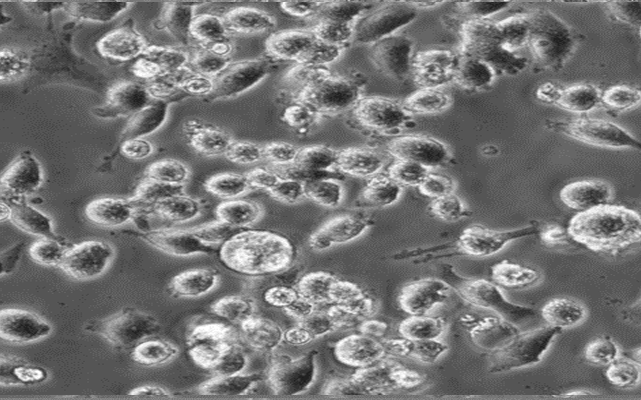

MIA PaCa-2;人胰腺导管癌细胞